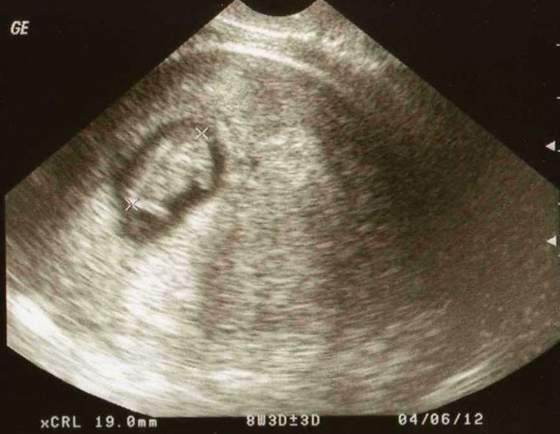

byłam na wizycie u gin no i musze się pochwalić maleństwem, które tylko pomachało i odwróciło się do nas pupą

to nasze maleństwo